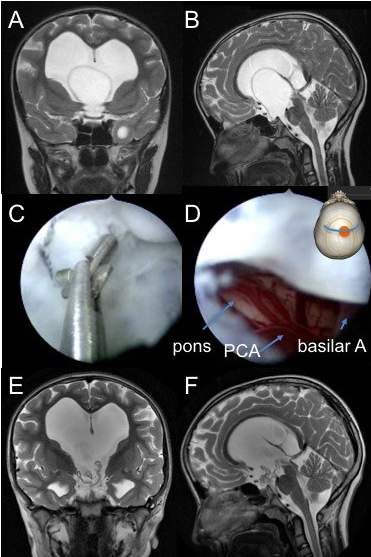

quatrième ventricule exclu

la reperméation de l’aqueduc est aisée en cas d’hydrocéphalie, car elle peut être réalisée du haut vers le bas. il ne faut pas dilater le ballon en raison d’un risque de troubles oculomoteurs.

la reperméation de l’aqueduc est plus difficile quand il s’agit d’un V4 exclu avec des ventricules sus-jacents bien drainés. il est préférable de laisser un cathéter en place comme stent pour éviter la re-sténose.